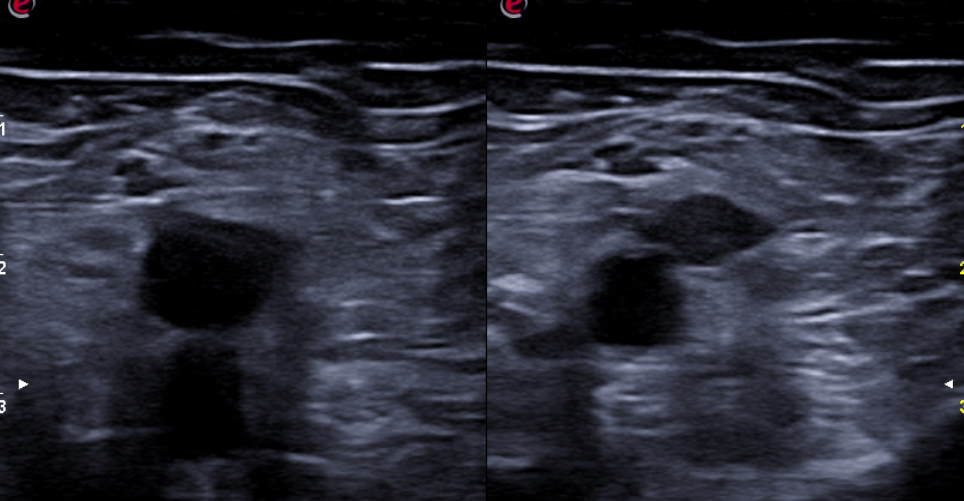

Expondremos la utilidad de la EC como herramienta en el manejo de los pacientes con diferentes tipos de dolor que atiende el Médico de Familia en las consultas diarias, urgentes, e incluso en los domicilios, en diversos escenarios clínicos a los que podemos enfrentarnos en nuestra práctica clínica habitual, desde un dolor visceral (abdominal, torácico, urológico o ginecológico), un dolor músculo-esquelético (traumático o no, con sospecha de fractura u osteoartrósico incapacitante), un dolor vascular (sospecha de trombosis venosa profunda, trombosis arterial aguda, aneurismático); ayudando a obtener una información crucial con un método no invasivo que nos ayudará a reducir la incertidumbre y orientar mejor el diagnóstico de nuestros pacientes e incluso nos podrá ser muy útil como herramienta con fines terapéuticos como en el caso de las infiltraciones ecoguiadas.